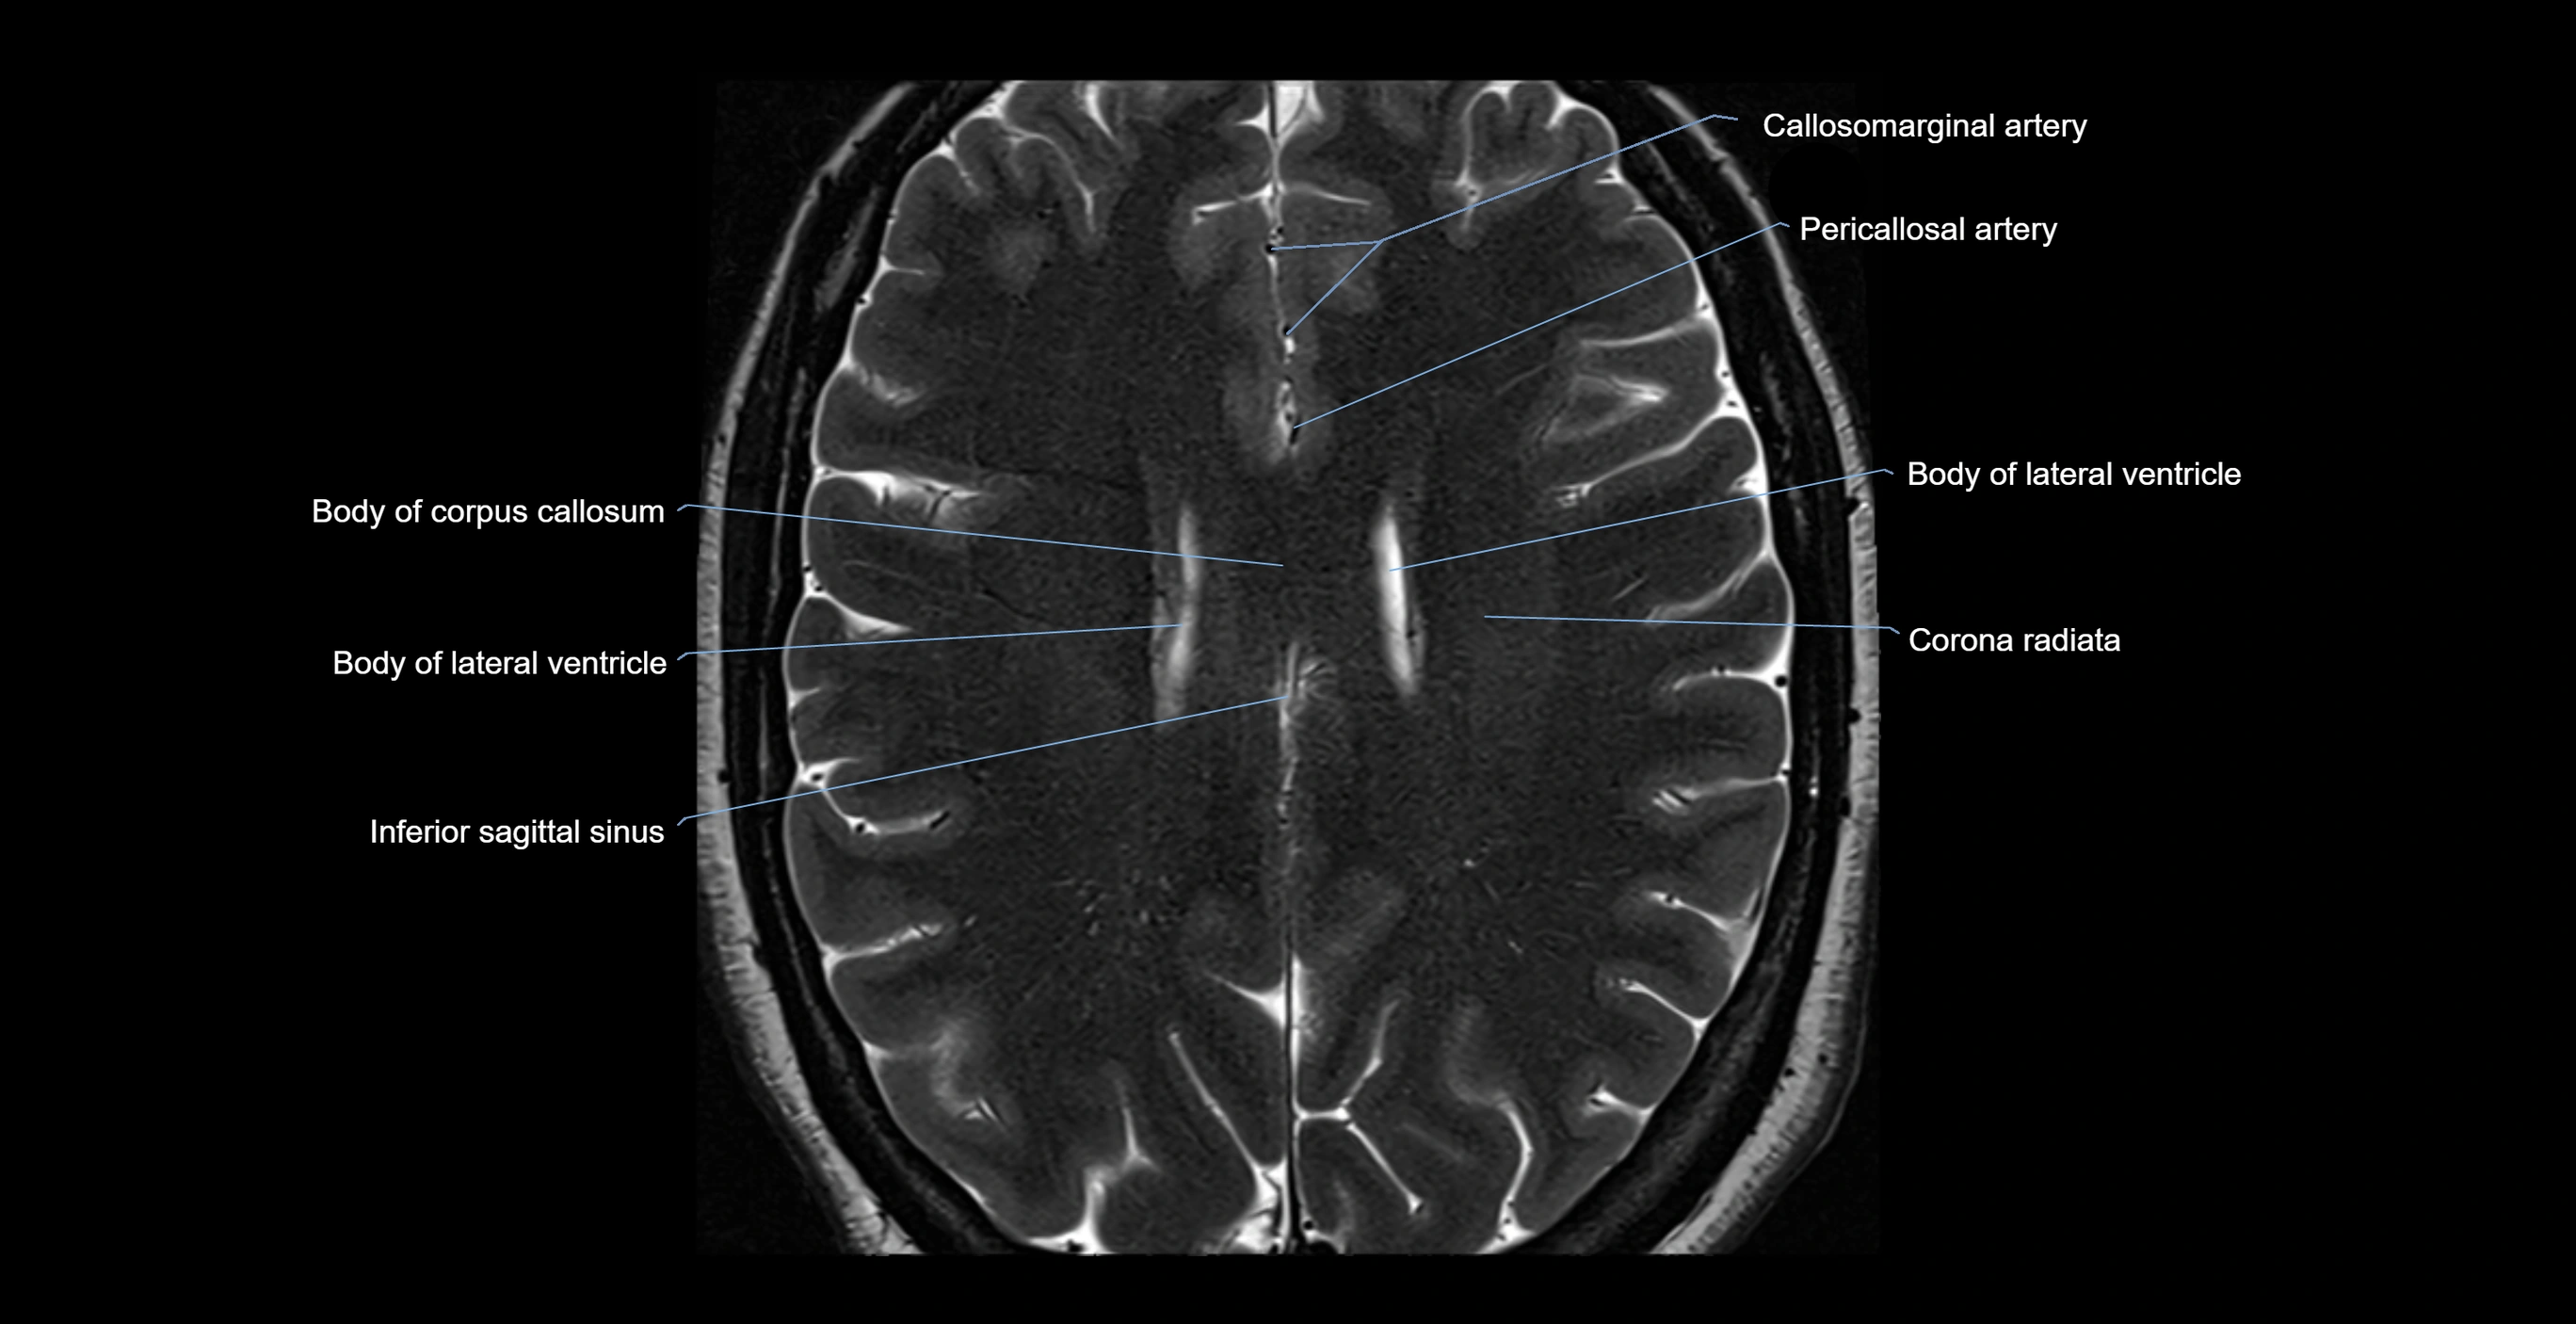

- Body of lateral ventricle

- Callosomarginal artery

- Corona radiata

- Inferior sagittal sinus